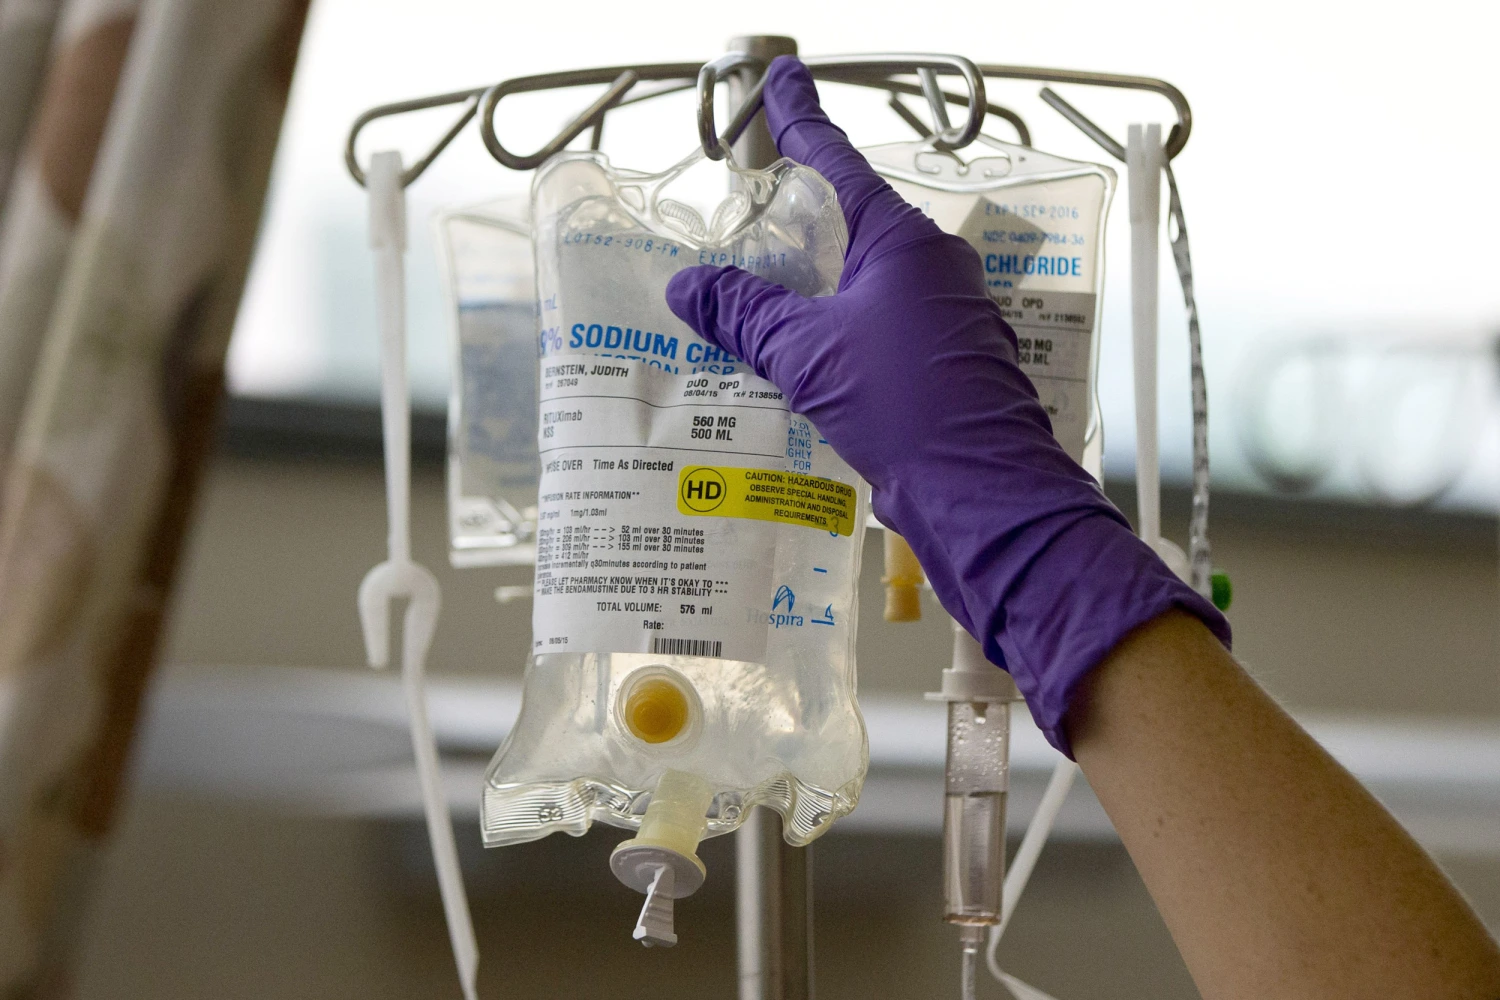

Heated chemotherapy may be viable treatment for ovarian cancer

Doctors say a promising treatment that delivers heated chemotherapy to ovarian cancer patients may be a better way to treat the disease.

Dr. Lewin on the Addition of HIPEC to Interval Cytoreductive Surgery in Ovarian Cancer

Sharyn Lewin, MD, FACS, discusses the utility of hyperthermic intraperitoneal chemotherapy in newly diagnosed advanced-stage ovarian cancer.

Holy Name Conducts Clinical Trial for Ovarian Cancer

Holy Name is offering a new clinical trial for ovarian, fallopian tube and primary peritoneal cancer…